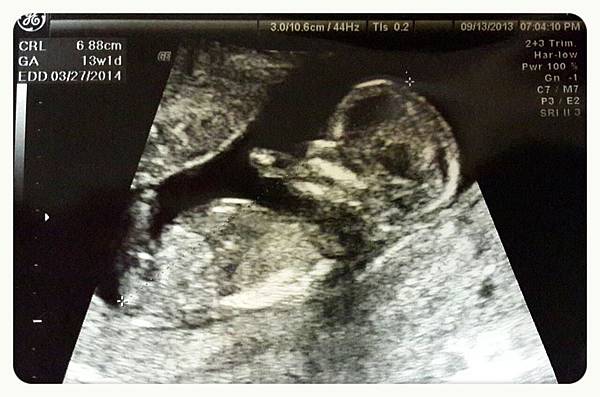

【13週又一天】

邁入12週的產檢,映入眼簾的是頭好壯壯、健康長大的洛克馬,這次和上次真的完全不一樣,對於初為人父母的我和螃蟹先生都好吃驚,醫生也很和藹可親的一一為我們介紹各個器官。在小蘿媽那個超音波還沒那麼發達的年代,對於小蘿每個月產檢的照片也大乎不可思議,她比我們我更雀躍、好奇,和小蘿媽、小蘿爸、小蘿可愛的弟妹們,還有螃蟹先生一起經歷著洛克馬成長日記,這種感覺真的幸福破表了啦!!!